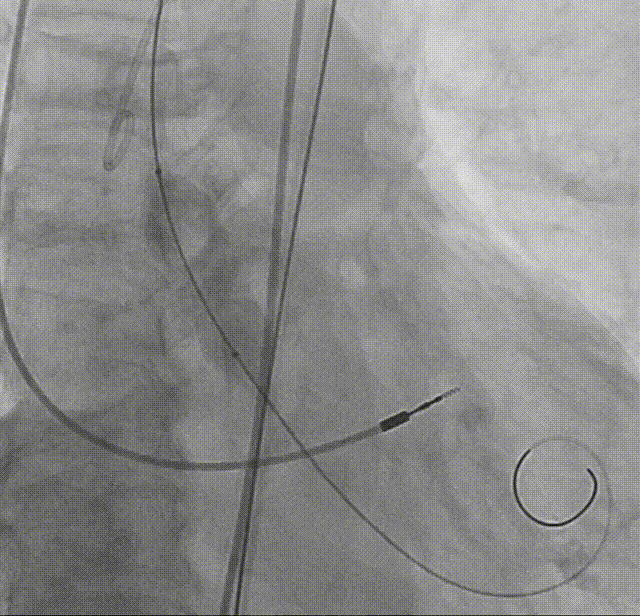

输送系统顺滑过弓

瓣下1mm初始定位

瓣膜释放至全展开位

全展开位评估:锚定区呈直筒状,瓣架中段微收腰,瓣膜形态佳

打平瓣架后造影评估:瓣架形态佳,植入位置可(接近0位),可见瓣周漏,冠脉显影可